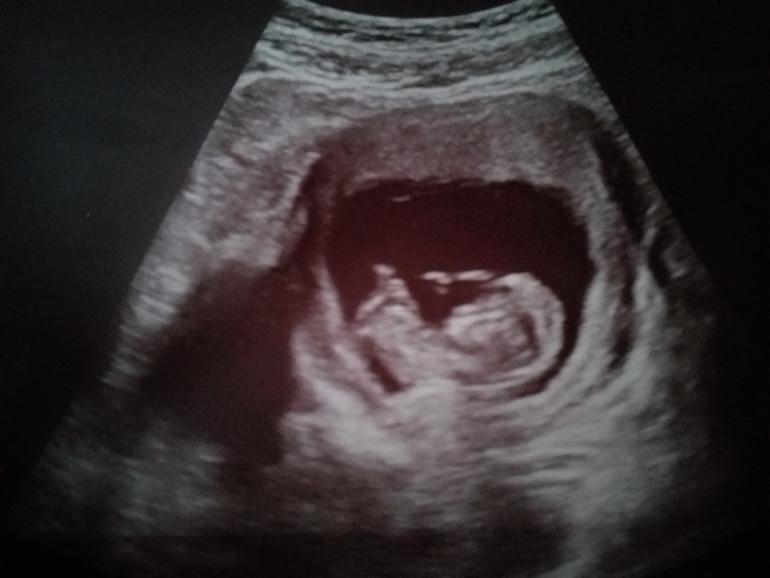

А куда смотреть то? Это ж лицо или нет 😁? Визуально по ощущениям, если это лицо, то больше на мальчишку похож.

Да никак) на этом сроке гениталии выглядят одинаково и отличаются только углом наклона) угол может высчитать хотя бы примерно только отличный узист на супер аппарате, а тут люди без мед.образования по смазаному фото определяют)

Дорогая автор поста, не настраивайтесь пока на конкретный пол, на таком сроке и тем более по фото невозможно это угадать) потерпите ещё немножко и в 16 недель вам скажут на УЗИ)

На таком сроке даже узисты 100% гарантии не дают, слишком велика вероятность ошибки. А вы хотите, чтобы форум по фотографии определил 🙄 Если пол нужно узнать прямо вот обязательно - сходите в 16 недель на УЗИ. В 16 пол уже называют точнее.

Тут не видно полового бугорка , только если гадать )

Оох, я вообще не представляю, как определчют пол, мне сколько узисты показывали, ничего не ясно, верила на слово 😁а в 12 недель мне неправильно определили, рано ведь ещё, более достоверно недель в 16 узнавать пол.